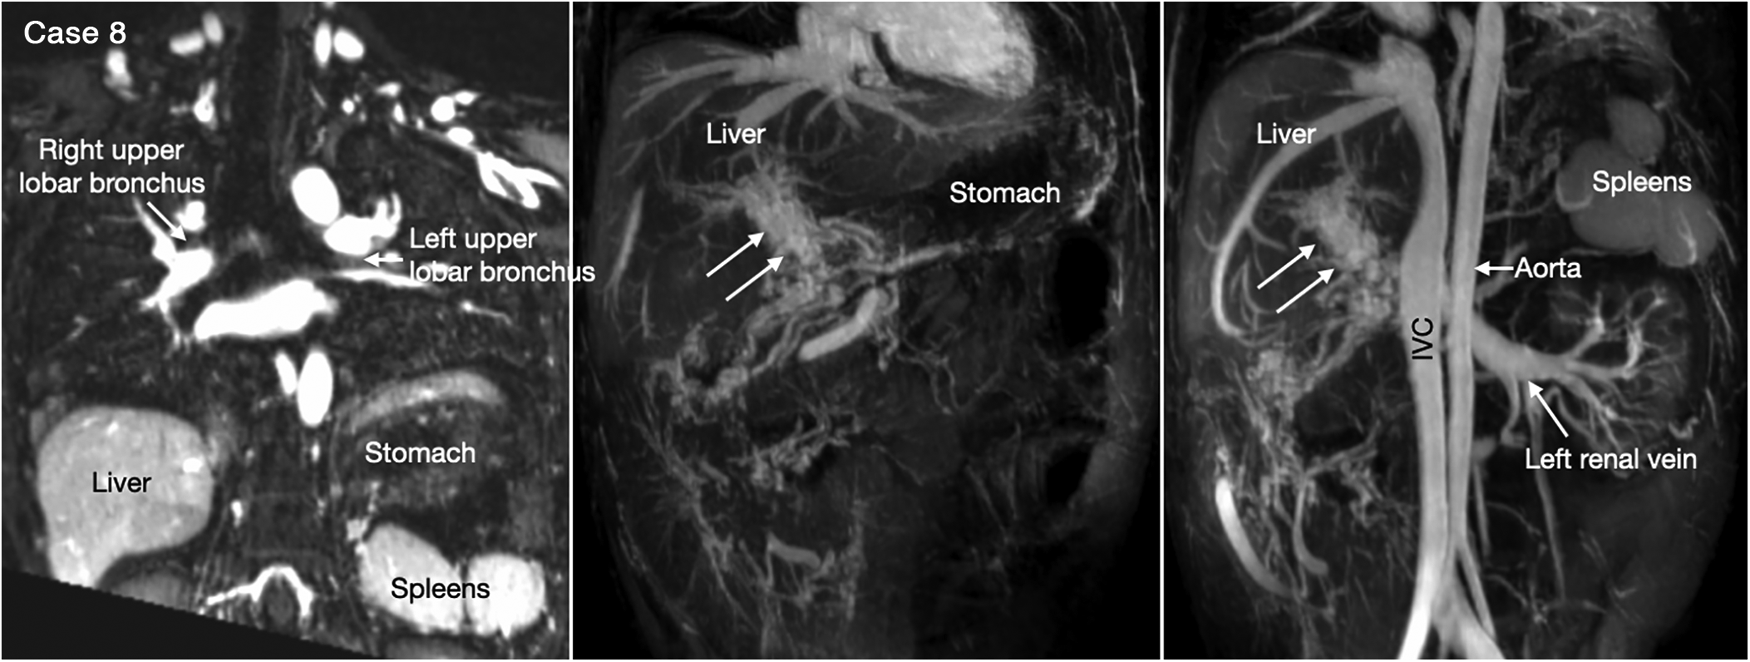

Figure 8

(Case 8). Cavernous transformation of the portal vein in a patient with left-sided polysplenia and otherwise normal body and atrial situs. Left panel shows bronchopulmonary situs solitus, and left-sided stomach and polysplenia. Middle and right panels show cavernous vascular plexus (two white arrows) along the expected course of the portal vein. Cavernous channels are also seen along the intestine. Right panel shows dilated renal vein functioning as portosystemic venous channel. Although cavernous transformation typically develops as a result of portal vein thrombosis, the association of polysplenia in this patient suggests that cavernous transformation is associated with congenital agenesis or hypoplasia of the portal vein. IVC, inferior vena cava.